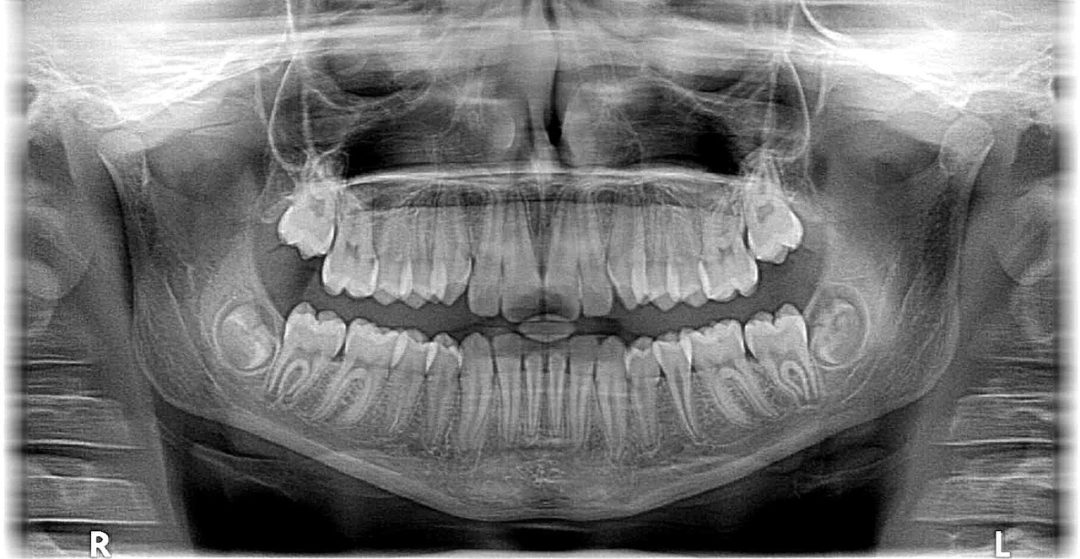

A panoramic X-ray will show your child's whole mouth in one X-ray - all the teeth in both the upper and lower jaws. These X-rays can be used to see emerging teeth, impacted teeth, or tumors. Cephalometric. A cephalometric X-ray shows both your child's teeth and the jaw and head by taking an image of the entire side of your child's head.

These X-rays can be used to look for problems with the tooth's root or the surrounding jaw bone as well as cavities. Panoramic. Panoramic X-rays help display your child's whole mouth in one X-ray, so all the teeth on the upper and lower jaws will be visible. Panoramic X-rays can be used to monitor your child's tooth development or to see.

They are made by a panoramic X-ray machine that rotates around your head. The panoramic X-ray is commonly used to detect wisdom teeth; acquire more information about jaw issues and missing or extra teeth; help identify abscesses, cysts, and tumors; and evaluate growth and development in children. This type of X-ray also provides information.